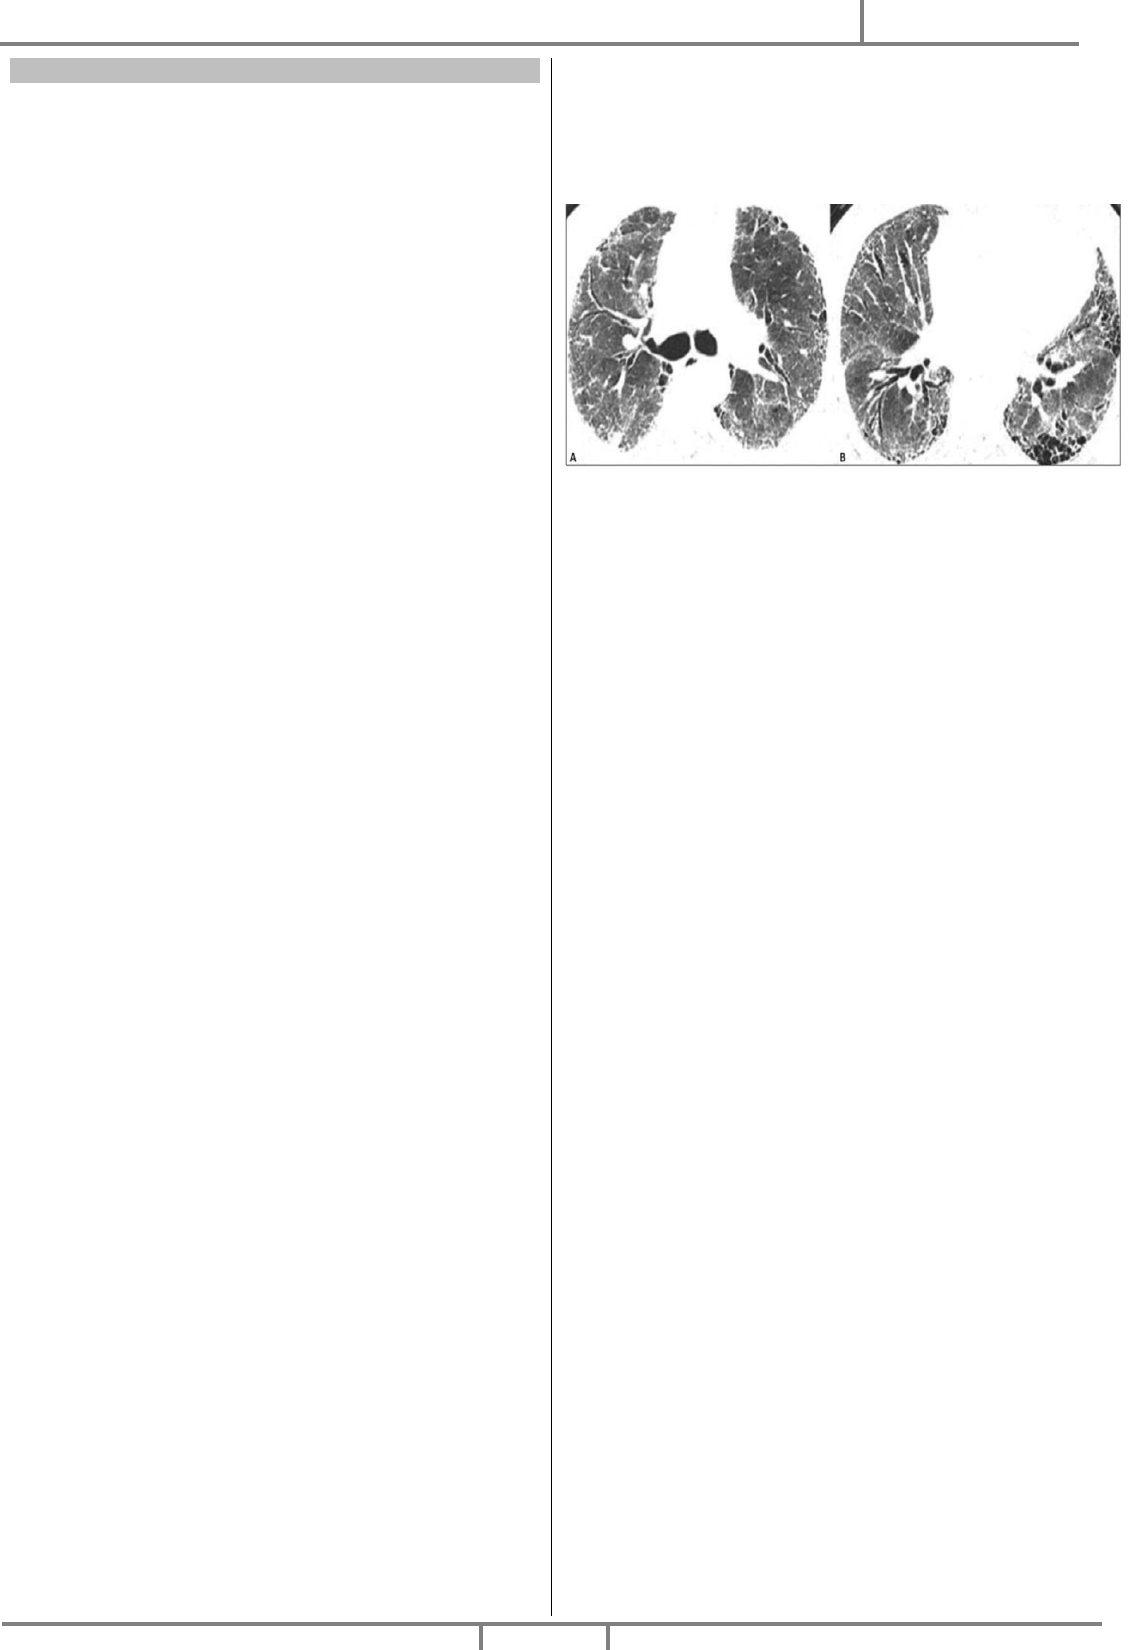

06. Você está diante de um paciente portador de fibrose

pulmonar idiopática, última tomografia mostrada abaixo, com

prognóstico reservado em relação à doença de base, familiares

conscientes da situação. Diante do quadro de exacerbação

aguda da doença, o que é melhor indicado?

(A) Ventilação mecânica não invasiva.

(B) Intubação traqueal e ventilação mecânica.

(C) Sedação com opioide, para conforto do paciente.

(D) Oxigenoterapia sob máscara de venturi e sedação.